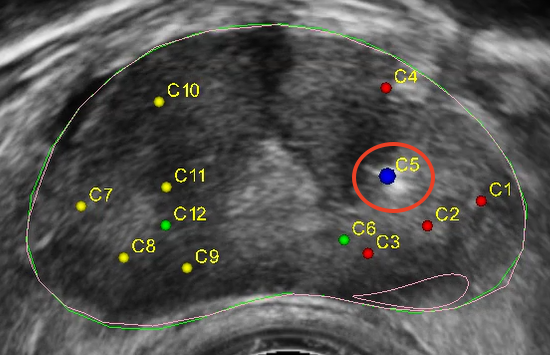

▲穿刺靶點(diǎn)

本次手術(shù)患者近日因身體不適到院檢查,進(jìn)行血清前列腺特異性抗原(PSA)篩查,結(jié)果顯示數(shù)值偏高,穿刺手術(shù)指癥明顯。在與患者及家屬溝通后牛少曦教授決定為患者行前列腺穿刺活檢術(shù),他表示,前列腺癌發(fā)病癥狀隱蔽,早期沒(méi)有任何癥狀,病灶不易被發(fā)現(xiàn),且與前列腺增生的臨床表現(xiàn)相似,往往會(huì)被患者、臨床醫(yī)生疏漏。在臨床,不少患者一經(jīng)發(fā)現(xiàn)已是晚期,治療棘手,嚴(yán)重的影響了患者預(yù)后。

牛少曦教授表示,Mona Lisa通過(guò)智能軟件制定方案,輔助臨床醫(yī)生更好地完成各項(xiàng)操作,不僅具備3D可視化MRI-超聲融合技術(shù),且其運(yùn)動(dòng)補(bǔ)償和針偏移位置補(bǔ)償技術(shù)也進(jìn)一步提高了穿刺手術(shù)的精準(zhǔn)性,解決了人工前列腺穿刺活檢時(shí)精準(zhǔn)度低、穿刺不均勻、并發(fā)癥較高等多種痛點(diǎn)。在MonaLisa的輔助下,臨床醫(yī)生可以更安全、精確、智能、高效地進(jìn)行活檢取樣,減少漏診率,減少穿刺針數(shù),減輕患者痛苦。該技術(shù)的推廣,將為男性前列腺惡性腫瘤疾病的精準(zhǔn)診斷和早篩提供技術(shù)支持,推動(dòng)提高了醫(yī)院前列腺穿刺操作技術(shù)水平,為前列腺癌患者帶來(lái)了福音。